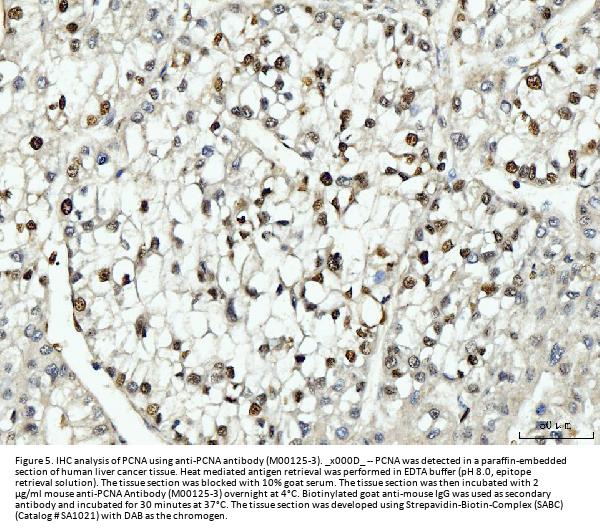

Immunohistochemistry(Paraffin-embedded Section), 2-5 μg/ml, Human, Mouse, Rat

Boster Bio Anti-PCNA Antibody Picoband® (monoclonal, 2G2) catalog # M00125-3. Tested in Flow Cytometry, IF, IHC, ICC, WB applications. This antibody reacts with Human, Mouse, Rat. The brand Picoband indicates this is a premium antibody that guarantees superior quality, high affinity, and strong signals with minimal background in Western blot applications. Only our best-performing antibodies are designated as Picoband, ensuring unmatched performance.